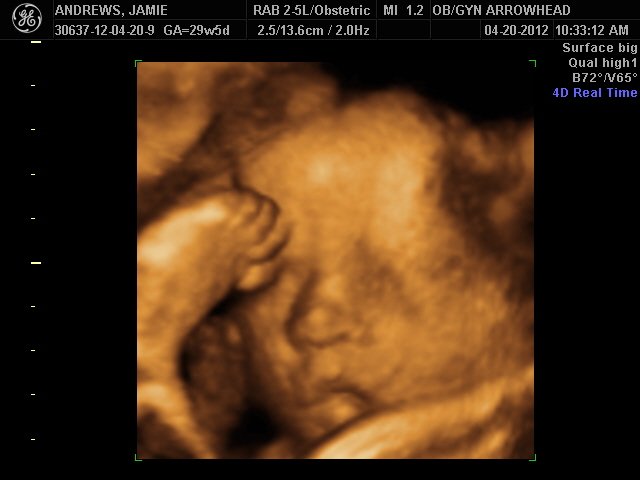

We offer complimentary 3D/4D Ultrasounds to all our OB patients around 30 weeks! The following photos are some examples of our work, shown with permission from our patients.